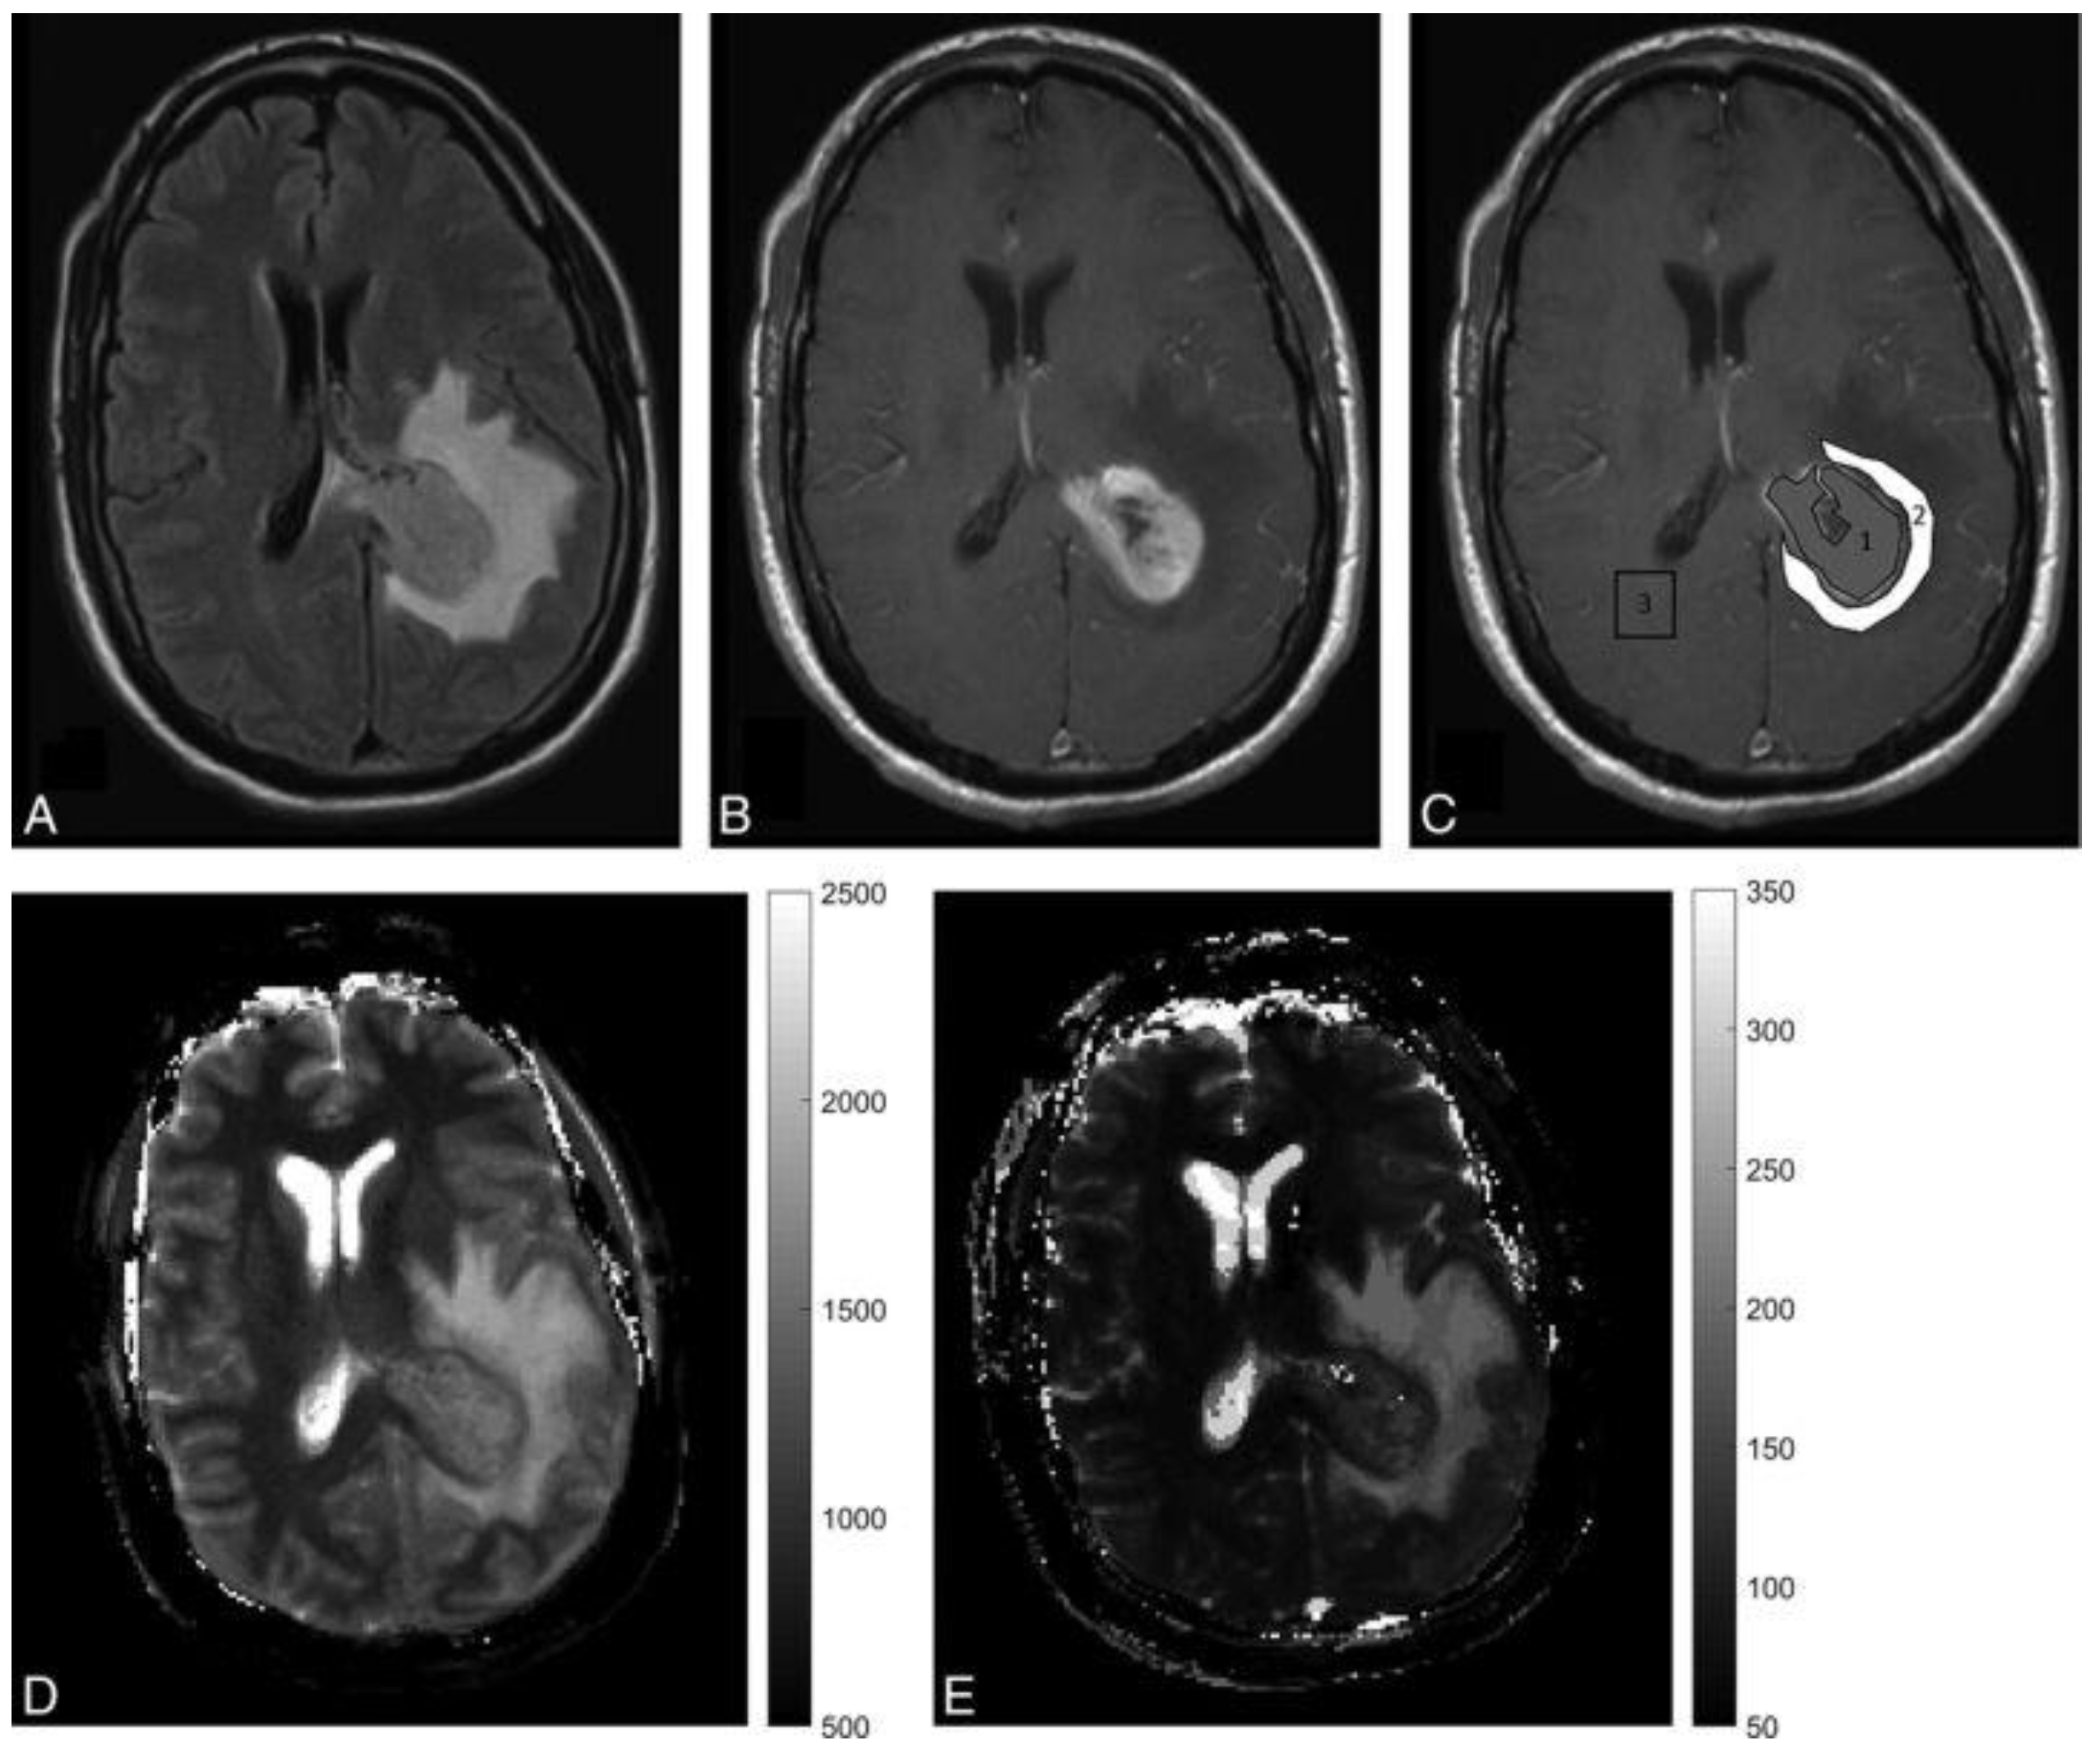

A preliminary study from Badve et al. suggested that MRF-derived T2 relaxation times from solid lesion components are higher in LGGs than in metastases (Figure 3) [40]. Differences in MRF-derived T1 relaxation times of peritumoral regions of GBMs and LGGs have also been identified [40]. In a later study, using the same data set, radiomic texture analysis was applied to further improve the differentiation accuracy [41]. MRF maps after texture analysis also showed the ability to predict patient survival time in the GBM cohort [41]. Considering the small sample size (31 patients), more evidence is needed to prove the diagnostic and prognostic reliability and repeatability of MRF. Similar studies were also conducted on paediatric and young adult patients [42]. MRF-derived T1 and T2 maps were significantly different for normal-appearing white matter, solid tumour, and peritumoral regions. MRF in children could help avoid potentially harmful, long-term retention of gadolinium-based contrast agents. The use of MRF could further avoid the risk of contrast allergy and minimises the need for sedation in children. The use of MRF has also been investigated in meningiomas. In a recent study, meningothelial meningiomas showed significantly higher T1 and T2 values than transitional and fibrous meningiomas on MRF images [43], whereas conventional MRI imaging and ADC values collected from the same set of patients detected no statistically significant differences between these tumour subtypes. Although larger cohorts are needed to validate the findings in these proof-of-concept studies, MRF is a promising potential QIB for investigating brain tumours. Repeatability and reproducibility of MRF for healthy brains have been tested under 1.5T and 3T at two different centres. Excellent repeatability and good reproducibility were reported [44]. More multicentre studies will be needed to establish the use of MRF more widely in common clinical settings, and parametric maps acquired by different MR vendors should also be compared.

Figure 3.

A 45-year-old male presenting with severe headaches and altered sensorium was later diagnosed with glioblastoma. (A,B) are FLAIR- and contrast-enhanced T1-weighted images from the clinical scan, which demonstrate a left parietal enhancing lesion with peritumoral FLAIR hyperintensity. (C) is a post-contrast T1-weighted image with ROI overlay. 1 shows a solid enhancing tumour region, while 2 shows a peritumoral white matter region. 3 in contralateral hemisphere denotes the contralateral white matter measurement. (D,E) are MRF-derived quantitative T1 and T2 maps showing a wider extent of disease. Reprinted with permission from ref. [40]. Copyright 2020 American Journal of Neuroradiology.